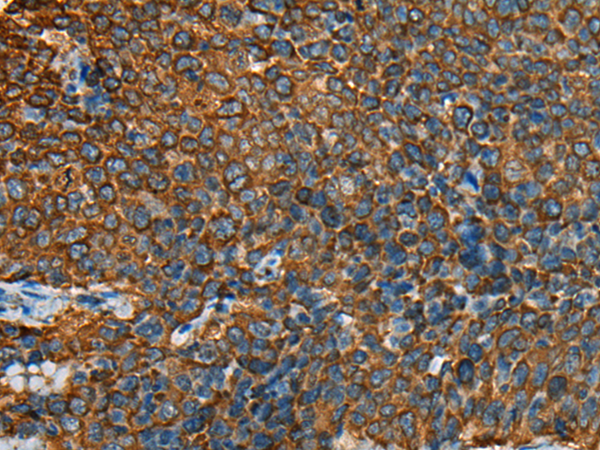

(Immunohistochemistry of paraffin-embedded Human cervical cancer tissue using YBX1 Polyclonal Antibody at dilution of 1:25(×200))